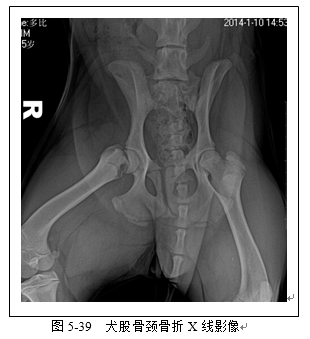

四肢骨骼X线评估常用于骨折检查(图5-36、5-37、5-38、5-39)以及关节脱位(5-40)检查。